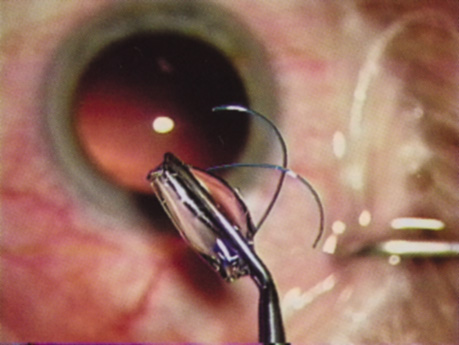

INTRAOCULAR LENS IMPLANTATION

At the turn of the century, the incidence of posterior capsular opacification (PCO), the most common untoward event after surgery, was plummeting as the result of a square edge design on the IOL optic. The haptics themselves had evolved from Prolene material to polymethylmethacrylate and then Alcon introduced a soft haptic on a single-piece acrylic platform. Every company developed an injector for improved IOL insertion, and industry was teaming up with innovative surgeons in developing a number of optic modifications. Attempts to achieve multifocality with diffractive optics had been introduced by 3M and their design team of Richard Lindstrom, John Sheets, and Robert Osher. This technology was placed on the back burner until Allergan developed the array multifocal IOL. Alcon purchased and improved the 3M defractive optic and introduced ReStor IOL on a single-piece acrylic platform. The surgical assault on presbyopia accelerated as Eyeonics developed the Crystalens, the first IOL with a pliable optic aimed at generating accommodation, a concept introduced a decade before by Spencer Thornton.33 A toric optic was developed by Staar Surgical; Pharmacia introduced Tecnis, the first spherical aberration-correcting IOL; and Alcon developed the first blue-light–filtering optic to provide macular protection. The once narrowly defined specialty of cataract and IOL surgery was exploding with new ideas and technologies. Smaller-incision IOLs were being designed that could be injected through <2-mm incisions. A host of surgeons, including Amar Agarwal, Jorge Alio, Richard Packard, Hiroshi Tsuneoka, Virgilio Centurion, Howard Fine, and Randy Olson, were exploring microincisional cataract surgery through 1.5-mm incisions by separating the sleeveless ultrasound tip from the irrigating chopper.